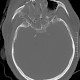

Strahlen schaffen Durchblick

Einen sehr gut gemachten Film über die Entdeckung und Anwendung von Röntgenstrahlen findet man auf der SWF3-Webseite "Planet Schule" mit dem Sendetitel: "Strahlen schaffen Durchblick".